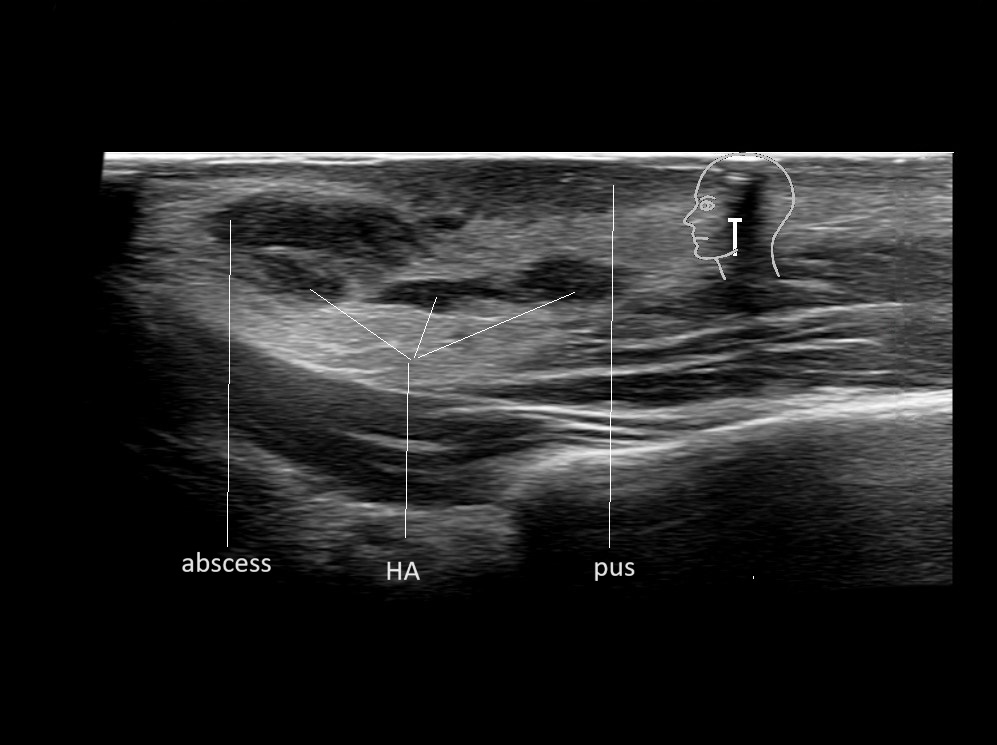

Filler injections in the parotid gland may go unnoticed, however, inflammatory reactions and abscesses may occur. Hypervascularity can be seen with color doppler. Filler deposits are supposed to be injected into the superficial fatty layer . The space to inject into this layer may be limited. Routinely we measure a width of 2-4 millimeters with sometimes subcutaneous layers being less than one millimeter thick.

Study the first image to recognize the different layers. If you are sure about the layers, swipe to the second image to view the answer (if applicable).